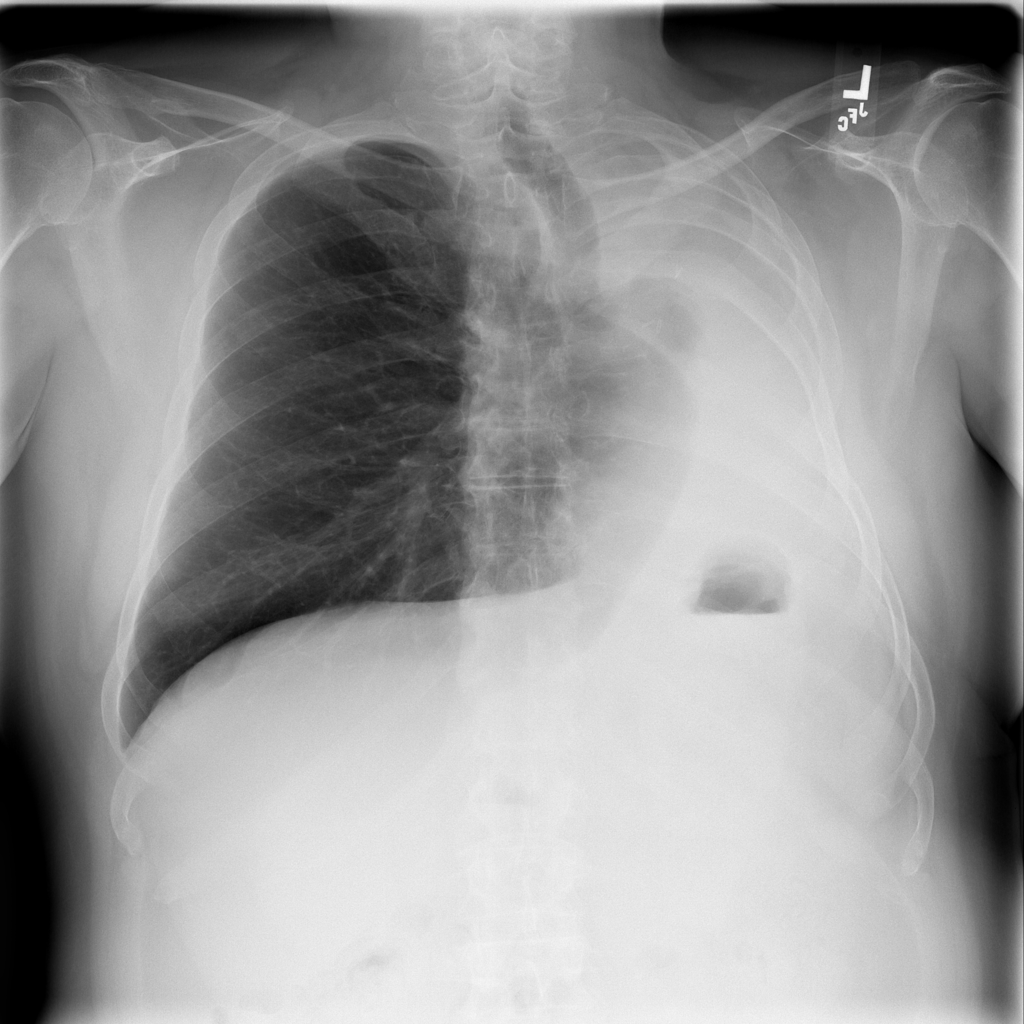

PAT-0ABD · IMG-000Hernia

PAT-0ABD · IMG-000

PA